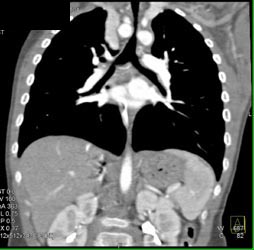

Airway Narrowing Due to Double Arch